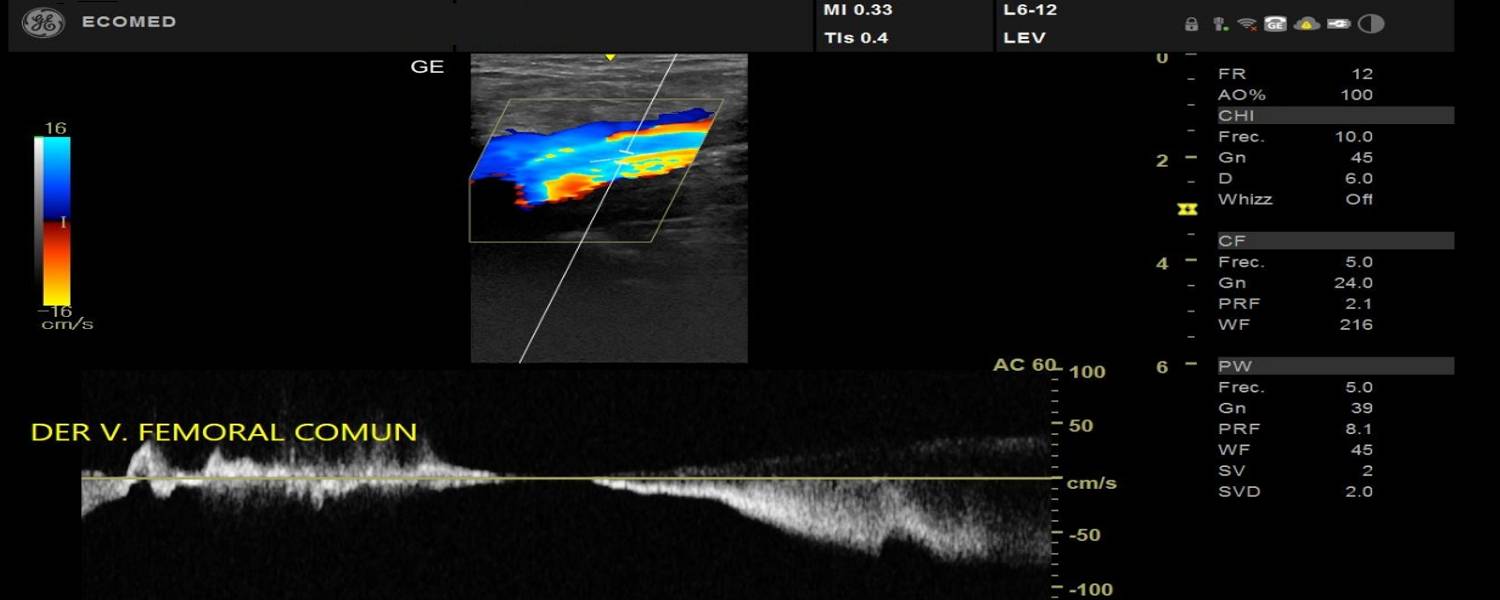

Qué es una ecografía?

Una ecografía es un examen médico que uiliza un transductor para capturar imágenes en vivo desde el interior de su cuerpo mediante ondas sonoras de alta frecuencia.

La ecografía le permite al médico ver problemas con órganos, tejidos y vasos sin necesidad de efectuar una incisión.